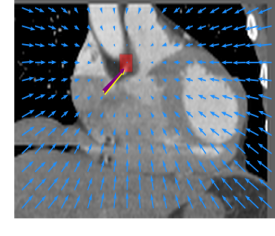

Finally, the proposed network was evaluated for the detection of five additional landmarks: the left coronary ostium, the bifurcation of the LM into the LAD and the LCx, and the origin of the left, non-coronary, and right aortic valve commissures (see Fig. 2). Fig 3 shows vector fields visualizing the predicted displacement vectors in three viewing planes in an image from the test set (for more results, see Appendix). Table 3 lists the Euclidean distance errors between the predicted landmark locations and the reference landmark locations. In addition, box-and-whiskers plots are shown in Fig 4. The best results were obtained for the origin of the right aortic valve commissure. Detection of the origin of the left aortic valve had the most narrow distribution. Outliers were seen during detection of the right ostium, the bifurcation of the LM, and the origin of the non-coronary, and the left aortic valve commissure.

Refer to caption Refer to caption Refer to caption

Figure 3: Vector fields visualizing the predicted displacement vectors in the axial, coronal, and sagittal plane in an image from the test set where detection of the right coronary ostium was performed. The magnitudes of the vectors should point at the right ostium, but they are rescaled for visualization purposes. The red squares indicate posterior probabilities larger than 0.5, obtained by the classification network for image patches. Reference and computed landmark annotations are indicated with a yellow and purple arrow, respectively.

Refer to caption Refer to caption Refer to caption Refer to caption Refer to caption Refer to caption Refer to caption Refer to caption Refer to caption Refer to caption Refer to caption Refer to caption Refer to caption Refer to caption Refer to caption Refer to caption Refer to caption Refer to caption

Figure 2: Vector fields visualizing the predicted localization vectors in the axial, coronal, and sagittal planes in images from the test set. The magnitudes of the vectors should point at the ostia, but they are rescaled for visualization purposes. The red squares indicate posterior probabilities that are larger than 0.5, obtained by the classification network for image patches. Reference and computed landmark annotations are indicated with a yellow and purple arrow, respectively. From the top to the bottom row, results are shown for detection of the right and left coronary ostium, the bifurcation of the LM, and the origin of the right, non-coronary, and left aortic valve commissure, respectively.